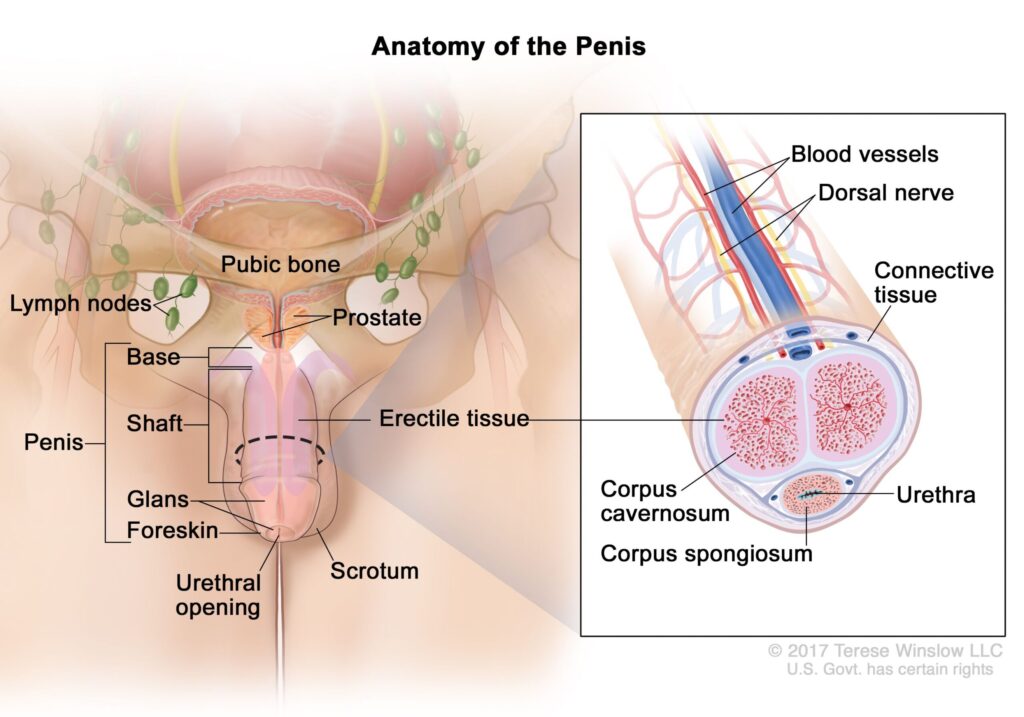

The real engine behind an erection isn’t the hormone.

It’s the penile nervous system.

Did you know that there are approximately 2,000 nerve endings responsible for male pleasure in your penis?

These nerves play a crucial role in your ability to feel and enjoy intimate sensations by transmitting vital information to your brain.

For example, when you’re about to engage in an intimate moment…

The nerve endings immediately detect any change, sending signals to the brain to trigger the erection response.

It’s like an internal warning system, guaranteeing your pleasure and performance. This system works like a valve: you get aroused and your penis automatically rises. At least that’s how it should be…

However, when it comes to erectile dysfunction, this system seems to fail.

The nerve tissue in the penis can deteriorate over time.

Factors such as age, lifestyle, underlying medical conditions and other elements can contribute to nerve damage.